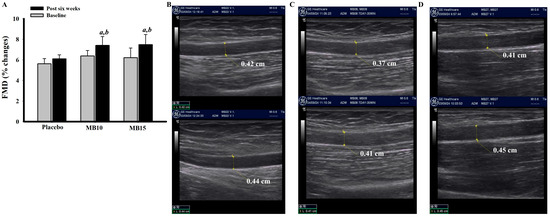

3.8. Effect of the Functional Protein Derived from MB Drinks on FMD

The flow-mediated dilation status of volunteers indicated no significant differences among the groups prior to the intervention. However, after six weeks of consuming the assigned products, the MB10 and MB15 groups demonstrated a significant increase in the percentage change of flow-mediated dilation (Figure 4A). This measurement was obtained and calculated from ultrasonographic images of the diameter of the brachial artery before occlusion and reperfusion in each group.

Figure 4. Flow-mediated dilation (FMD) of volunteers before and six weeks after the intervention (A). Representative ultrasonographic image elucidates brachial artery diameter before occlusion (upper panel) and reperfusion (lower panel) of placebo group (B), MB10 (C), and MB15 (D) performed after six weeks of intervention. Data are presented as mean ± SEM of %changes of baseline (n = 9/group). a p > 0.05 when compared with baseline, b p < 0.05 when compared with placebo (post six weeks).